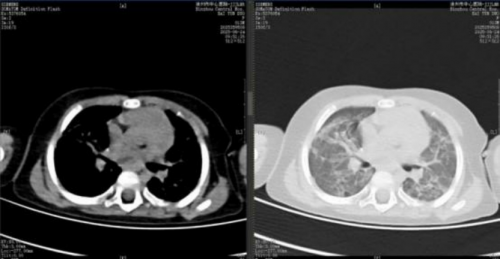

4.影像学持续好转:2025 年 6 月 24 日复查胸部 CT(见图 6),结果显示肺部病变较前继续好转。8 月 10 日复查胸部 CT,显示双肺病变已明显吸收(见图7)。

图 6

图 7

通过上述综合干预,患儿病情逐步迎来转机。动态影像学监测清晰展现了肺部病变的持续改善:从5 月 28 日 CT 显示的“双肺炎性病变较前(5-14)有吸收”,到 6 月 24 日“较前好转 ”,直至8 月 10 日复查 CT 见病变明显吸收,客观印证了治疗的有效性。在此过程中,患儿呼吸功能显著恢复,成功脱离有创通气,序贯经鼻高流量氧疗及鼻导管吸氧,最终于8 月 13 日生命体征平稳出院。本例救治经验表明,对于传统治疗方案反应不佳的儿童重症肺炎及 ARDS,在综合支持基础上,早期并分阶段应用西维来司他钠,能有效改善氧合、减轻肺损伤,可能成为避免肺移植、改善预后的关键决策。其疗效与本例中观察到的 PaO₂/FiO₂比值提升及影像学改善相符,为共识的临床实践提供了有力佐证,但其在儿童群体的广泛应用仍需更多研究进一步验证。